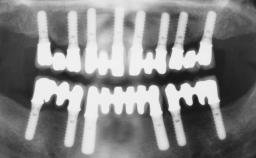

# of Implants 6

Type of Implants One-Piece

Defining Characteristics Fully edentulous upper jaw to be rehabilitated with four or more implants

Modality 6+ implants with immediate loading